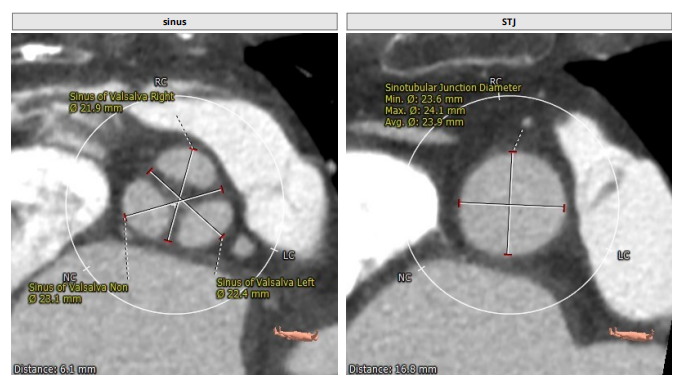

术前CT评估

整体情况

瓣环:16.9mm,左室流出道:16.7mm

STJ:23.9mm,升主动脉:31.4mm

瓣叶增厚 右冠高度:10.9mm,左冠高度:9.5mm